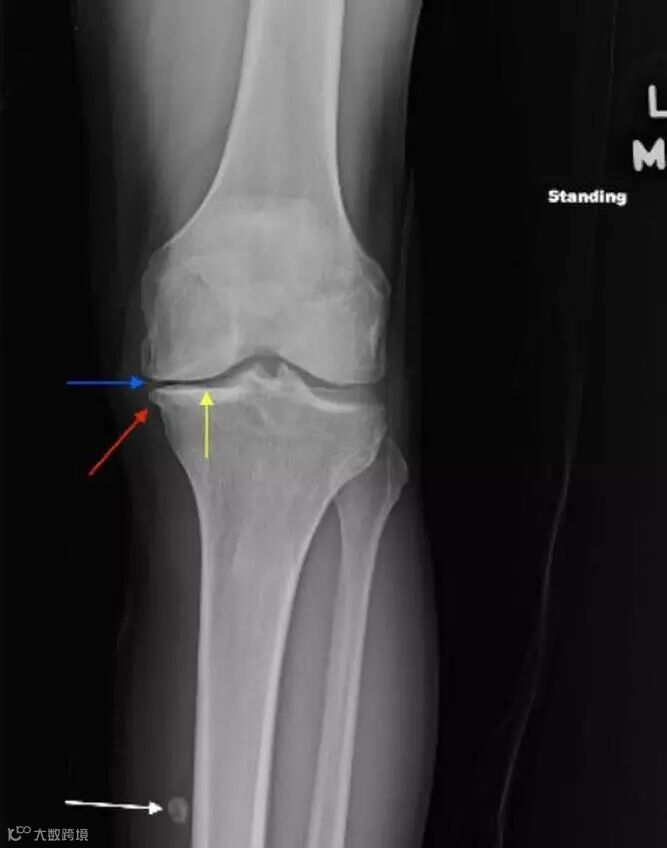

Frontal view of the left knee demonstrates joint-space narrowing (yellow arrow), osteophyte formation (red arrow), and chondrocalcinosis (blue arrow). There is a calcified body (white arrow) within the inferior recess of a dissecting Baker cyst.